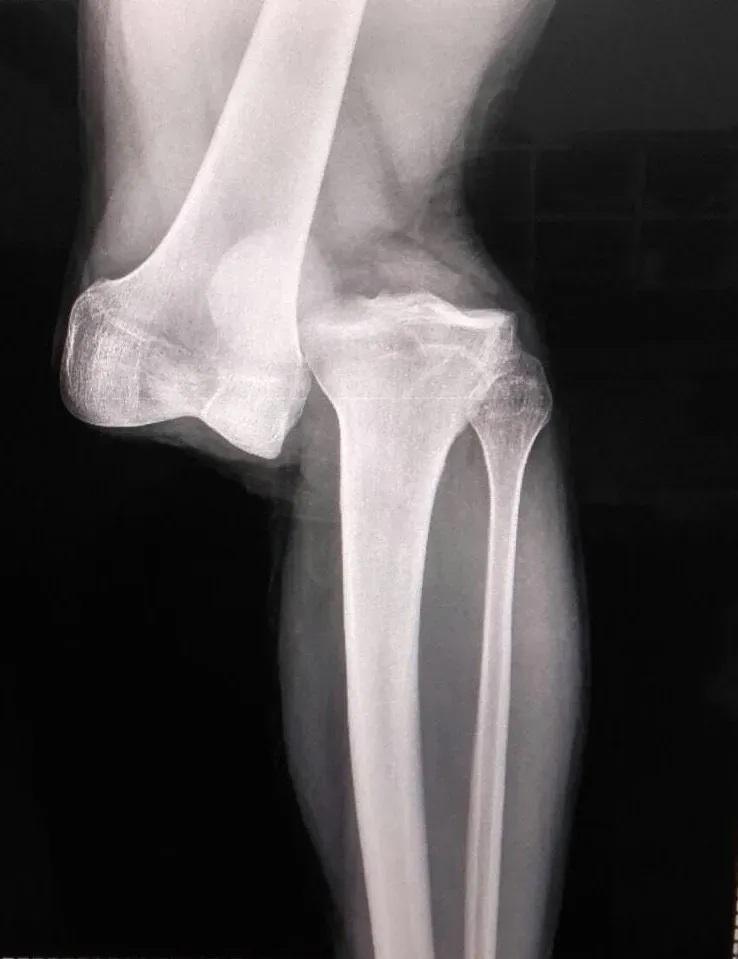

Todo ocurrió en el encuentro entre Argentinos Juniors y Fluminense por los octavos de final del torneo internacional. De entrada en el segundo tiempo, Sánchez fue pisado por el histórico defensor brasileño. Esto último le provocó una ruptura total de la rodilla.

Tras el encuentro, el médico y secretario general del elenco trasandino afirmó que "en 23 años como médico nunca vi una lesión así. Es casi una separación del fémur y el peroné. Hay rotura de cruzado, anterior, posterior… Hay que hacer una reconstrucción".

El propio cuerpo médico del club señaló que Luciano Sánchez deberá someterse a una recuperación de, cómo mínimo, 10 a 12 meses. Solo para recién empezar a pensar en volver a las canchas de fútbol. Un balde de agua fría que en las últimas horas sumó una impactante imagen de la radiografía del jugador.